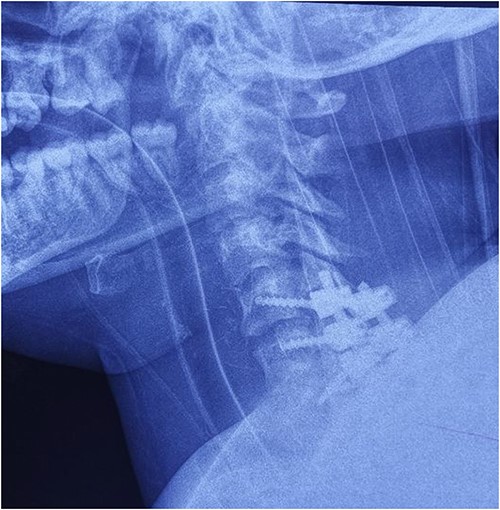

On the fourth day after the injury, the patient was conscious, on low doses of vasopressor support. What was surprising was that in her conscious state she had weakened abduction of the left shoulder, while the right arm and legs were completely plegic (ASIA A). We decided to perform posterior reduction and stabilization from the level of C5 to T1 (Figs 3–5). On the first postoperative day, a follow-up X-ray of the cervical spine was performed (Figs 6 and 7).

Intraoperative finding after repositioning and stabilization: screws placed into the C5-C7 massae laterales and the T1 pedicles; fixation performed with titanium rods.

Cervical spine X-ray postoperatively – lateral view: properly positioned osteosynthesis material.